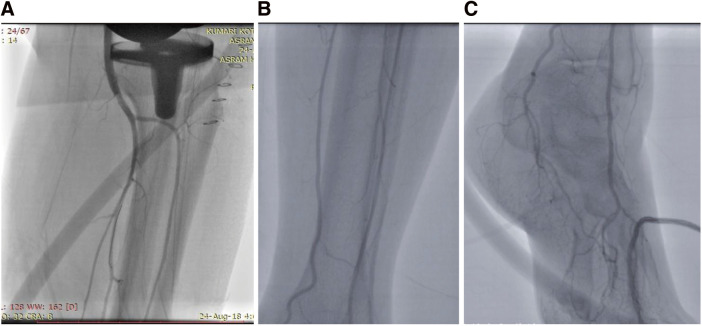

目的:本研究的目的是探讨全膝关节置换术(TKA)后腘动脉血栓形成导致急性肢体缺血(ALI)的罕见并发症的发生、临床特征、治疗方法和结果。方法:对1020例TKA手术进行回顾性研究。通过临床评估和动脉多普勒检查确定ALI病例。周围血管成形术使腘动脉再通。评估其表现、并发症及处理策略。结果:1020例TKA中,ALI 5例,占全部TKA病例的0.49%。女性优势和左侧表现是值得注意的观察结果。大多数患者在8小时内出现症状,伴有足部下垂到筋膜室综合征等多种并发症。除1例外,其余患者均经吸血栓及球囊扩张后恢复。结论:TKA的腘动脉血栓形成是一种罕见但可能致命的并发症,因此早期识别和干预以减轻不良后果非常重要。在我们的研究中,就有效管理和减少手术并发症和发病率而言,血管内治疗已成为首选方式。

Objectives: The objective of this research was to examine the occurrence, clinical features, treatment approaches, and results associated with a rare complication of thrombosis of the popliteal artery after total knee arthroplasty (TKA), leading to acute limb ischemia (ALI). Methods: A retrospective study on 1020 TKA procedures spanning 5 years. Cases of ALI were identified through clinical evaluation and arterial Doppler studies. Peripheral angioplasty was done to recanalize the popliteal artery. Manifestations, complications, and management strategies were evaluated. Results: Among the 1020 TKA cases, 5 cases of ALI were identified which accounts for 0.49% of all TKA cases. Female predominance and left-sided presentations are notable observations. Most patients presented within 8 hours of symptom onset with diverse complications ranging from foot drop to compartment syndrome. Except for 1 case, all patients recovered with thrombosuction and balloon dilatation. Conclusions: A rare but potentially fatal complication of TKA is popliteal artery thrombosis leading to ALI so it becomes important for early recognition and intervention to mitigate the adverse outcomes. In our study, endovascular treatment has emerged as the preferred modality in terms of effective management and reducing complications and morbidity from surgical procedures.